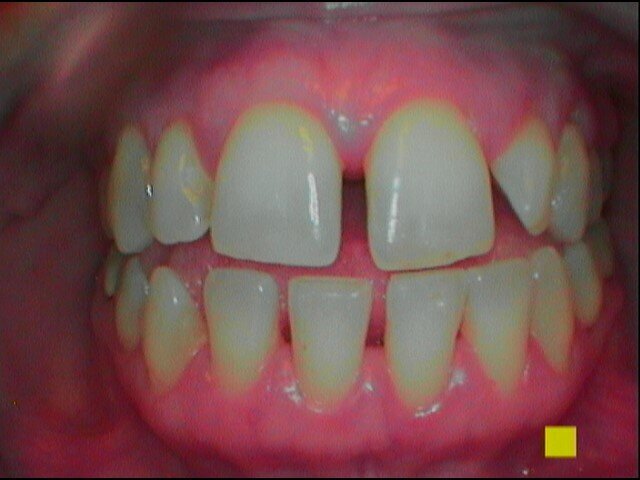

Proponiamo al paziente di igienizzare il dispositivo ortodontico in maniera efficace e più ergonomica: chiediamo di disorganizzare il biofilm batterico attraverso l’azione meccanica di uno spazzolino idoneo con setole a fiamma rigide. Dopo aver sciacquato il dispositivo ortodontico sotto un flusso costante di acqua, chiediamo di asciugare il dispositivo per applicare a 5 cm di distanza un’efficace spray igienizzante all’olio ozonizzato, IalozonClean (Gemavip), ideale per la capacità di proteggere il dispositivo da batteri, funghi, lieviti e virus a lungo termine. I suoi ingredienti, e in particolare l’olio d’oliva ozonizzato, il cetylpiridinio cloruro oltre ad igienizzare ,deodorano il dispositivo ortodontico e permettono di lasciare che rimanga del suo colore originale. Si raccomanda al paziente di non metterlo in lavastoviglie e di non farlo bollire e di usare altre soluzioni o materiale disinfettante per la pulizia e la conservazione dello stesso per non danneggiarlo, opacizzarlo e farlo ingiallire. Condividiamo con il paziente la necessità di igienizzare la mascherina ortodontica ogni volta che ha necessità di toglierla come ad esempio durante i pasti.

Per il mantenimento del sorriso luminoso, abbiamo consigliato di implementare la seduta di igiene con uno sbiancamento a base di aloe vera (moro white smile). Al controllo il paziente riferisce assenza di percezione di odori sgradevoli nel cavo orale e sul dispositivo invisibile con sensazione di freschezza dopo l’utilizzo del collutorio e di aver spazzolato e igienizzato la mascherina ortodontica con frequenza .Gli indici clinici sono PI pari al 10%, BoP negativo, PDD medio fisiologico (Figg. 14-16).